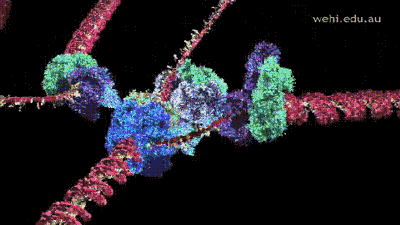

纳豆激酶溶栓机理是:

纳豆激酶通过刺激血管内皮细胞产生

组织型纤溶酶原激活剂(t-PA),

t-PA将纤溶酶原激活为纤溶酶,

溶解纤维蛋白,直接溶解血栓;

同时将人体内的尿激酶原激活为尿激酶,

尿激酶与tPA一同激活纤溶酶原,

达到溶解血栓。

由此可见,

纳豆激酶在直接溶解已经形成血栓的同时,

还能激活增强人体自身的溶栓能力,

从而起到揿平稳的溶栓作用。